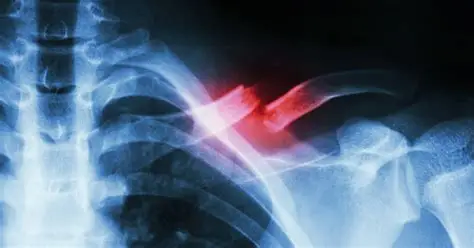

Shoulder And Arm Fractures